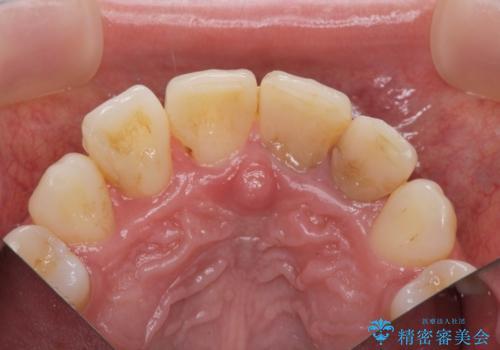

- 神経の死んでしまっている前歯の変色の改善を求めて来院されました。

根管治療をしたのち時間が経過して変色が目立つ歯と、レジン充填が複数箇所に及んでいる歯も同時にオールセラミック治療を行っていくこととなりました。